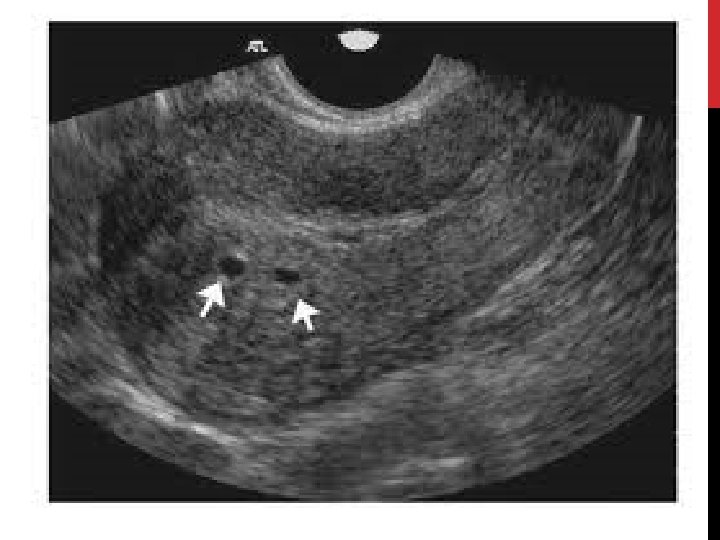

ECHOGRAPHIE PELVIENNE PAR VOIE ENDOVAGINALE: Examen de 1ère intention: • Signes directs: • Kyste endométriosique. • Nodules sous péritonéaux antérieurs et postérieurs. • Adénomyose: éléments anéchogènes au sein du myomètre. • Image hypo échogène, discrètement hétérogène. • Signes indirects: • Pseudo kyste péritonéal: trouble de résorption du liquide péritonéal (adhérences). • Hydro/hématosalpinx: obturation tubaire complète. • « kissings ovaries » : infiltration rétractante et adhérentielle des nodules des LUS. + échographie rénale à la recherche d’une hydronéphrose, surtout si présence d’un nodule de l’espace antérieur.

BILAN COMPARTIMENT MOYEN • Concerne l’utérus, les annexes, les ligaments ronds, larges et le vagin. • Ovaires: 20 -40%. • Informations majeures: • Présence d’endométriome. • Perméabilité tubaire. • EEV: seul examen nécessaire dans la majorité des atteintes. • Se 89%, Spé 91%, VPP 84%, VPN 94, 5%. • Évaluation de la réserve ovarienne (CFA) • Recherche dilatation tubaire. • IRM: • Pour éliminer une EPP associée ou pour diagnostic différentiel kyste ovarien. • Se 90%, Spé 98%, précision 96%. • CR: nombre, taille endométriomes, recherche dilatation urétérale, rapport avec les organes voisins, recherche de salpinx, éliminer EPP. • HSG: • Évaluation de la distension et perméabilité tubaire • Limites: invasif, risque de FN (spasme tubaire), risques infectieux. • gold standard: cœlioscopie + test de perméabilité tubaire.

ADÉNOMYOSE (2) • Diagnostic clinique: • • • Examen normal dans 65% des cas. TV: utérus augmenté de volume, dur, fibreux, à contours réguliers, +- sensible pendant les règles. Diagnostic radiologique: • Echographie endovaginale: Se 82, 5%, Spé 84, 6% • • • IRM pelvienne: Se 77, 5%, Spé 92%, VPN 88, 5%, VPP 92% • • Utérus volumineux non expliqué par la présence de fibromes. Asymétrie des parois myométriales antérieure ou postérieure. Aspect strié du myomètre. Zone hétérogène myométriale, lacunes hypo échogènes myométriales, nodules hyperéchogènes. Épaississement ZJ en T 2 > 12 mm. Présences de zones focales hypo intenses. Spots hyper. T 2 myométriaux. Echographie 3 D: • • • Anomalie de la ZJ avec zones hyperéchogènes. Perte de l’aspect triangulaire de la cavité en coupe coronale. Vascularisation en peigne.